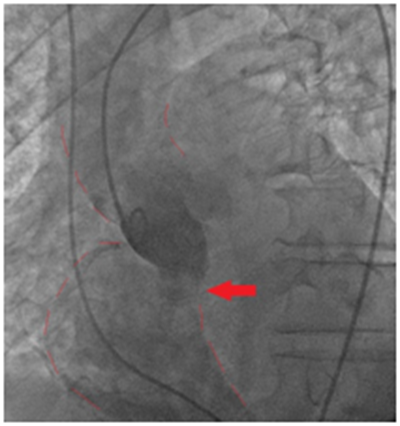

A 79years old man was admitted to the hospital because of dyspnea and fever. Eleven days before admission, the patient had been diagnosed of a Klebsiella Oxytoca urinary tract infection initiating antibiotic treatment with ciprofloxacin. He had history of hypertension, dyslipidemia and multiple urological interventions with internal urethrotomy and dilatation due to urethral stenosis. Clinical examination at admission was normal without signs of heart failure. Electrocardiogram (ECG) showed complete heart block requiring implantation of a temporary pacemaker. Laboratory analysis showed leukocytosis with left deviation and elevated C-reactive protein suggesting an infectious process. In this context, a transthoracic (TTE) (Figure 1) and a transesophageal echocardiography (TEE) was performed showing a large pediculated vegetation on a bicuspid native aortic valve that extends to the left ventricle (LV) and right atrium (RA) (Figure 2). A high velocity jet was observed across the right atrium simulating pulmonary hypertension. Aortic wall was complicated with an aneurysm. Rest of valves and biventricular function were normal.2

Figure 1 Image of a large vegetation in the right atrium in a transthoracic echocardiography view.